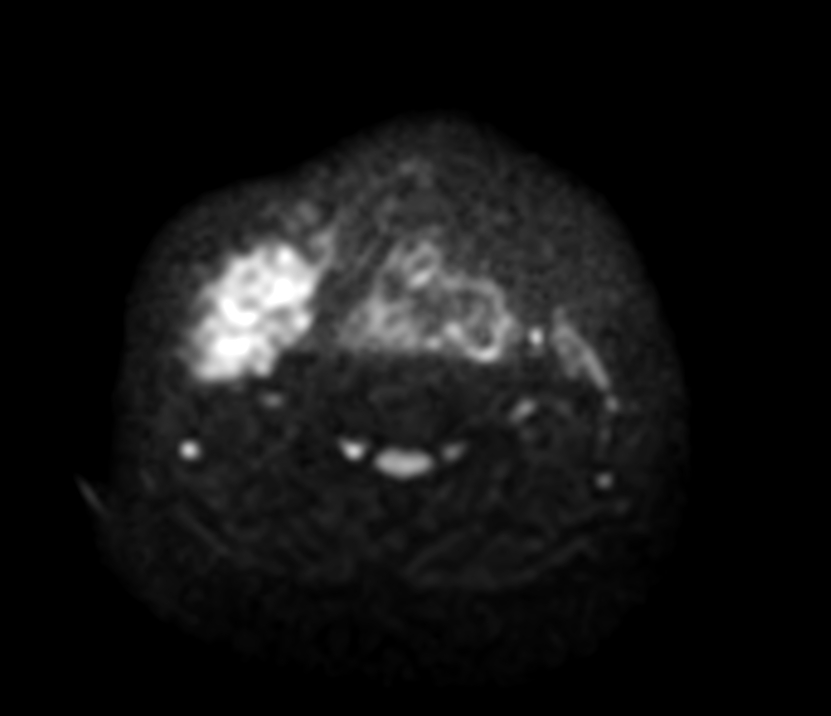

Axial DWIBS (b700)